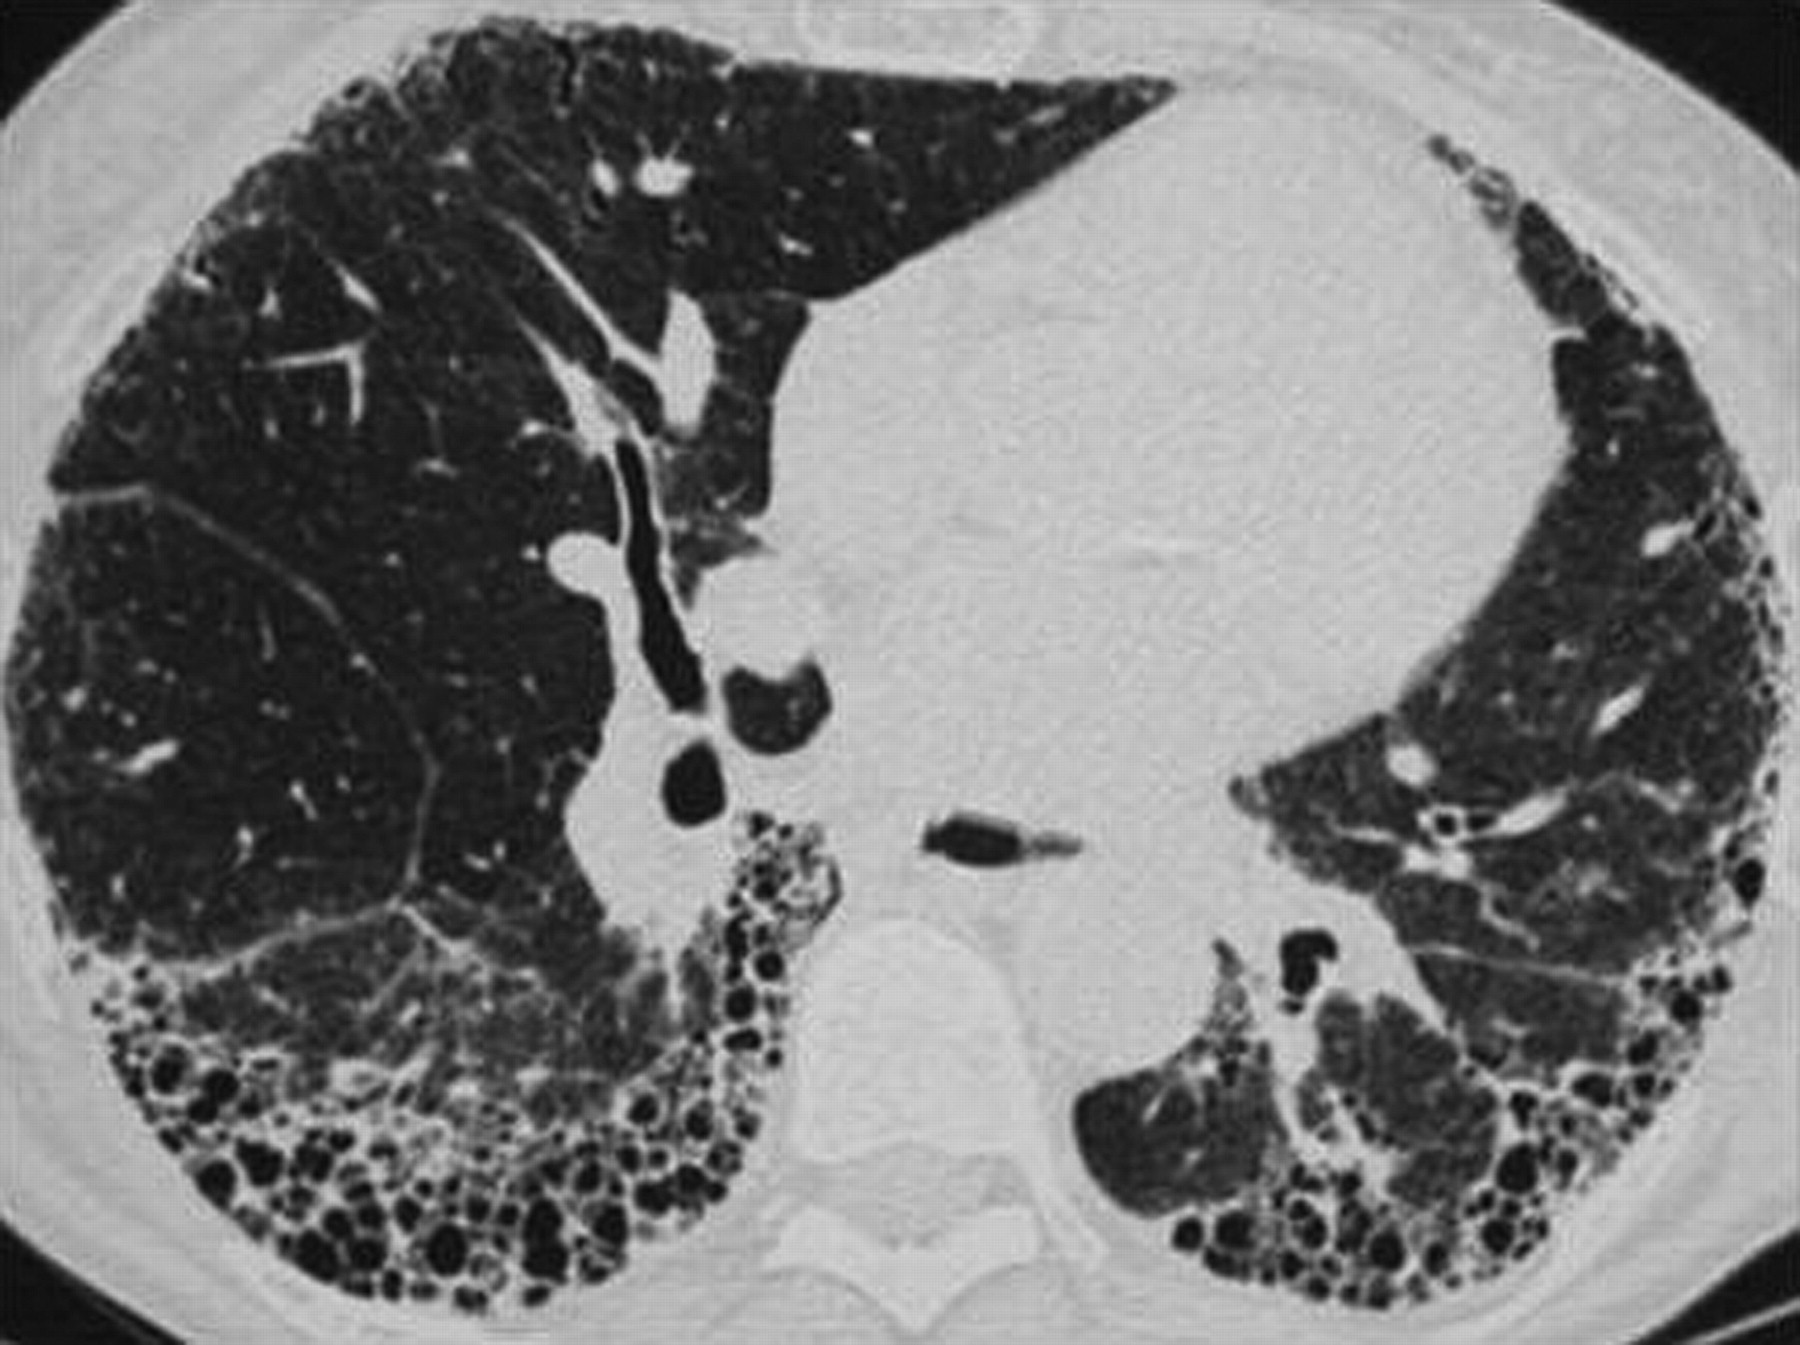

_硬皮病肺纖維化

_特發性肺纖維化的高清CT圖像

_雙肺肺纖維化的

_雙肺肺纖維化肺灶

_特發性肺纖維化ct表現圖